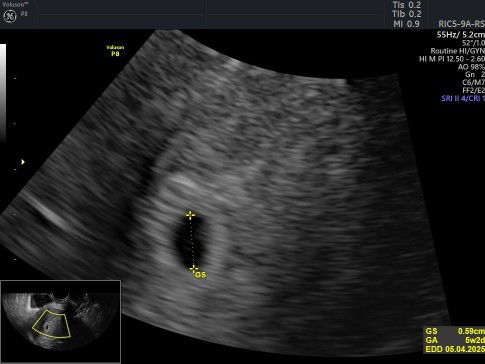

Hpht 2 Juli, rencana USG nya pas udh 9-12week krn emang ini kehamilan ke2 Tp trnyata udh 3 kali flek coklat, trs kmrn sempat flek darah sedikit Krna takut riwayat kandungan lemah, akhirnya sy usg saja Transvaginal. Wkt hamil pertama aja full penguat kandungan tiap bulan smpai usia kehamilan 7 bulan. Pas kmrn USG taunya bnr memang di area rahim ada darah tp sedikit bukan yg tanda2 pendarahan alhamdulillah, masih kantung saja, disuruh balik lg sekitar sebulanan lg aja, kalau memang berkembang bakalan ada bayinya Kalau kosong brarti ya tidak berkembang Semoga sehat ya bun, kehamilan ke 2 ga begitu berasa cuma kdng kram perut aja krna cape jg mungkin 😅 #hpht2juli #hplapril2025 #garisdua